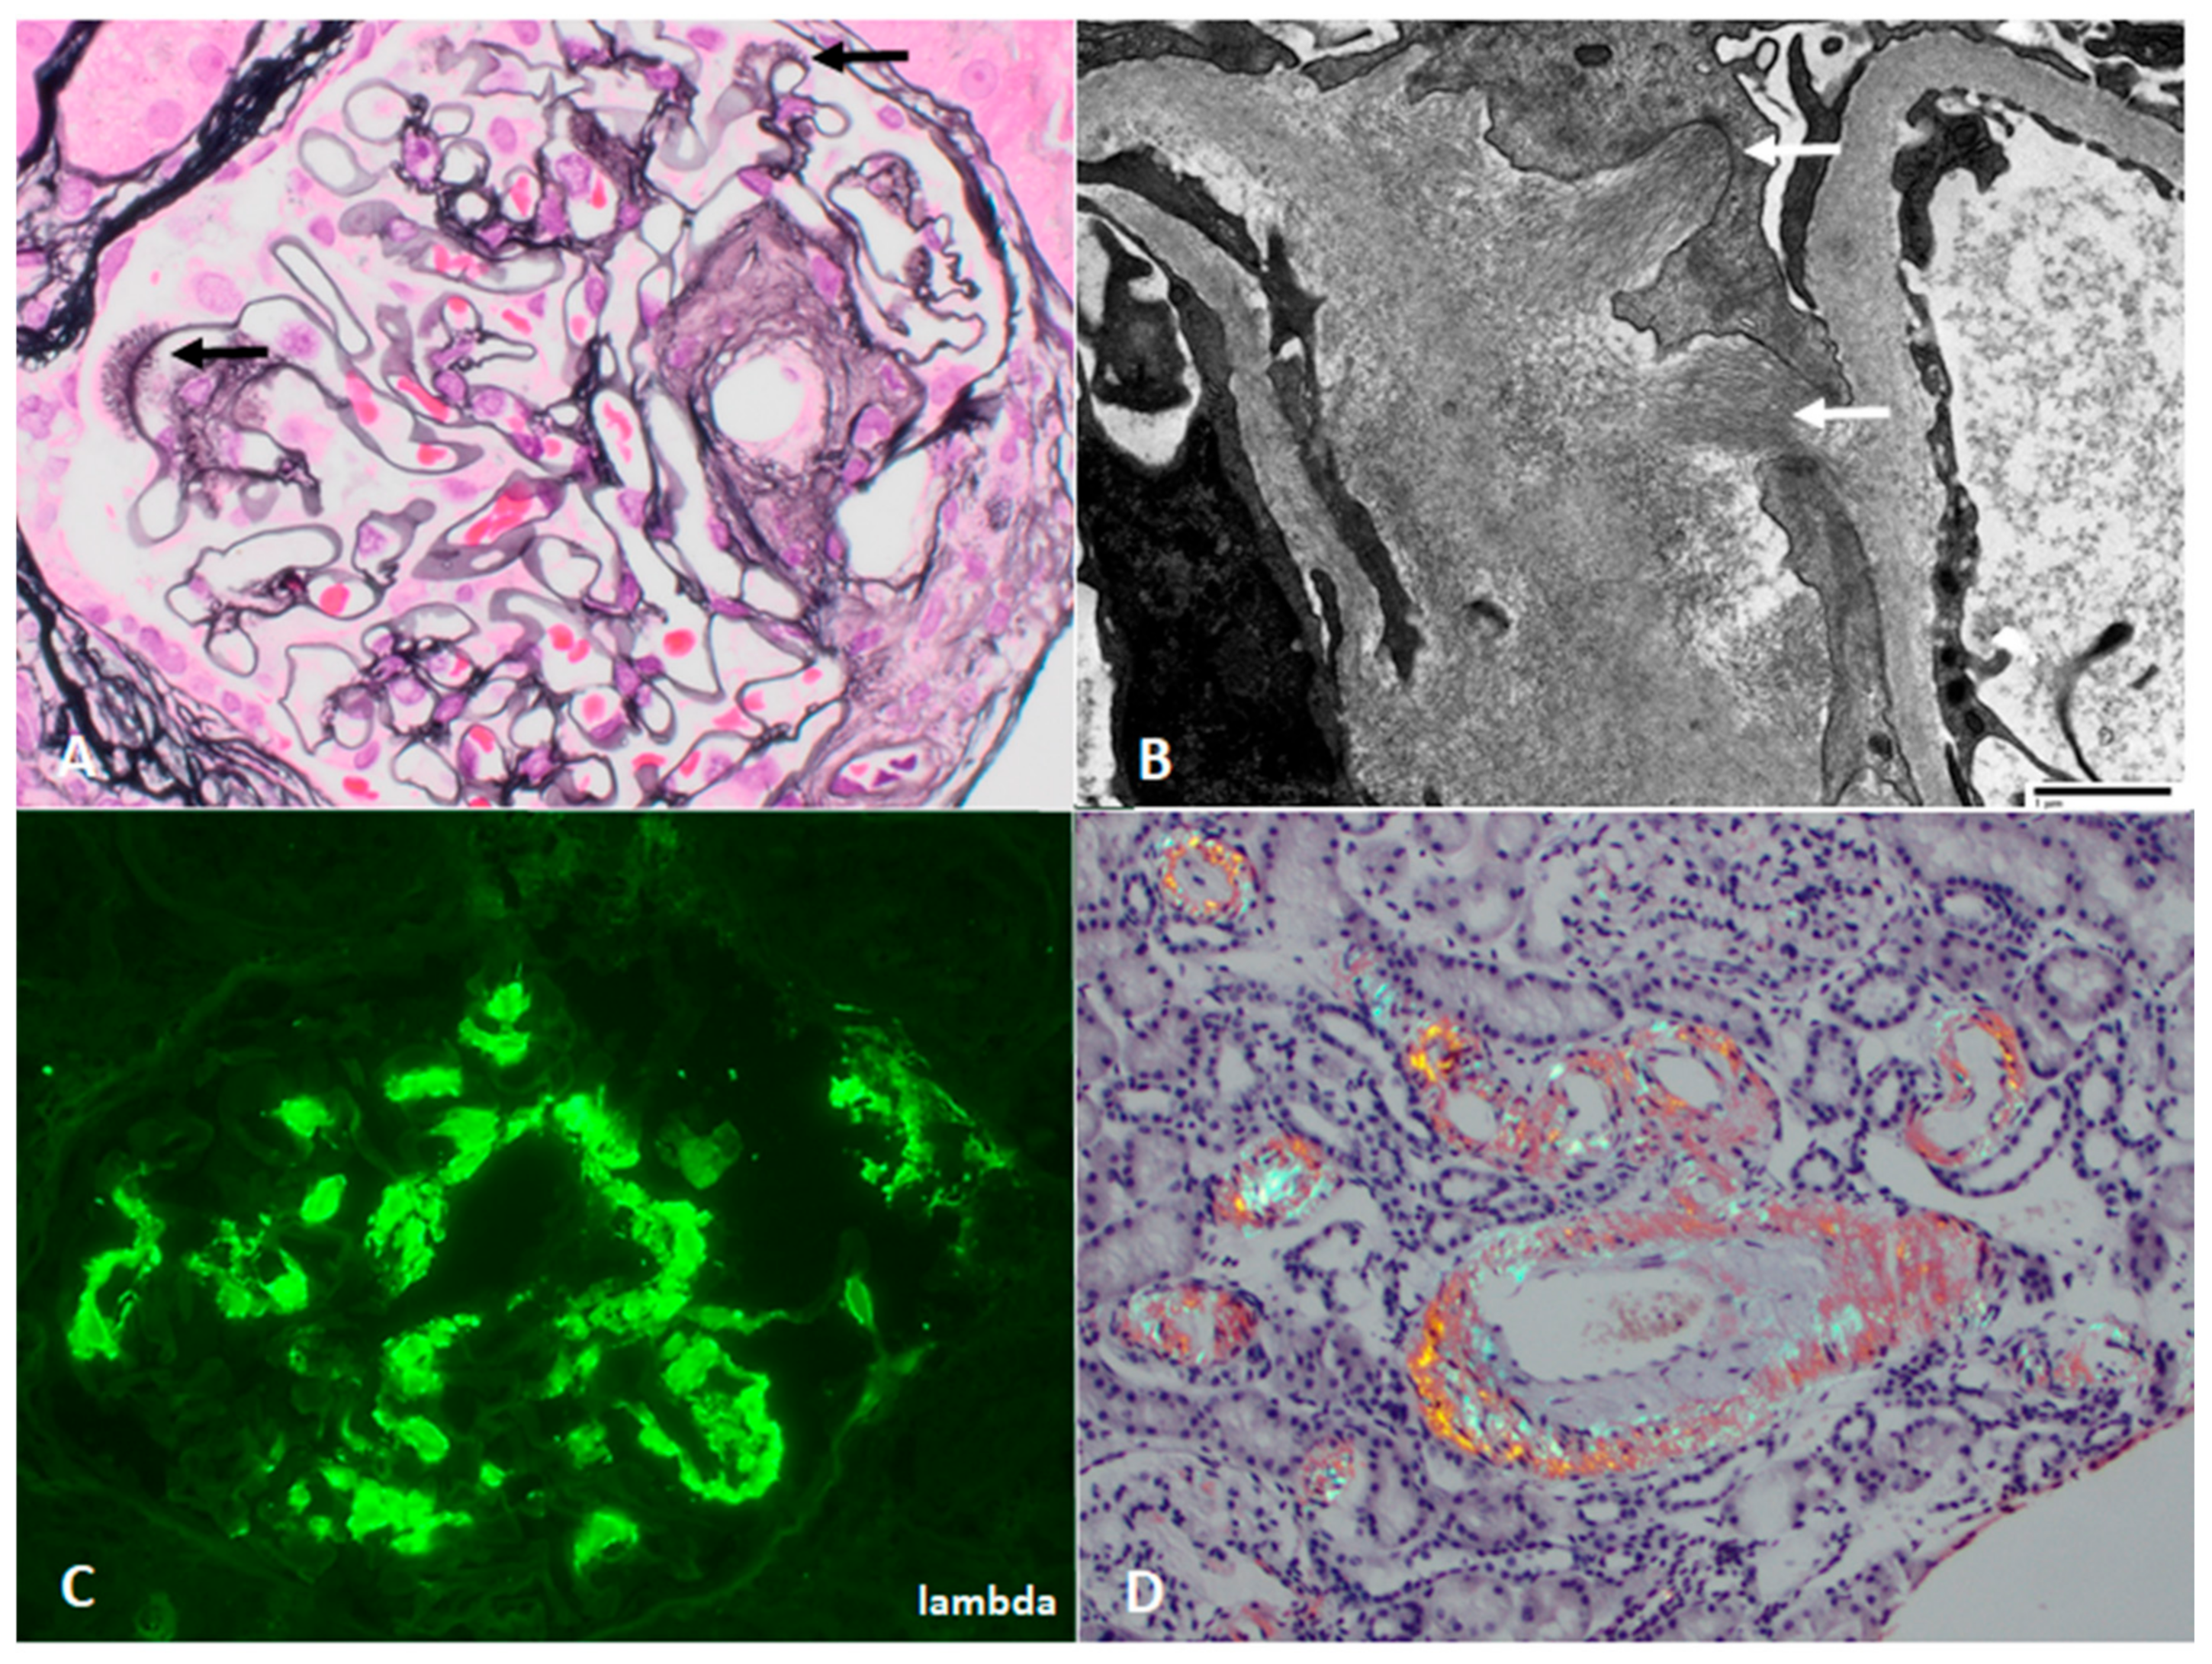

On kidney biopsy, cryoglobulinemic GN (Figure 4) has an endocapillary to membranoproliferative pattern of injury, with influx of monocytes and neutrophils. Large intracapillary “plugs” of immune complexes may be present, as well as extraglomerular leukocytoclastic vasculitis. Immunofluorescence shows irregularly distributed, chunky capillary wall staining for the monoclonal protein in type 1 cryoGN, commonly IgG and one light chain, and the addition of IgM in type 2 cryoGN. Electron microscopy shows occasionally large subendothelial and mesangial deposits, some with microtubular organized substructure.

7. Monoclonal Immunoglobulin Deposition Disease

Monoclonal immunoglobulin deposition disease (MIDD) (Figure 5) may be light chain (LCDD), heavy chain (HCDD), or both (LHCDD), and is characterized by a diabetes-like glomerulosclerosis with thickened tubular basement membranes by light microscopy, widespread tubular basement membrane and glomerular staining for the monoclonal Ig by immunofluorescence (Figure 5), and fine “powdery” subendothelial and tubular immune deposits by electron microscopy [95].